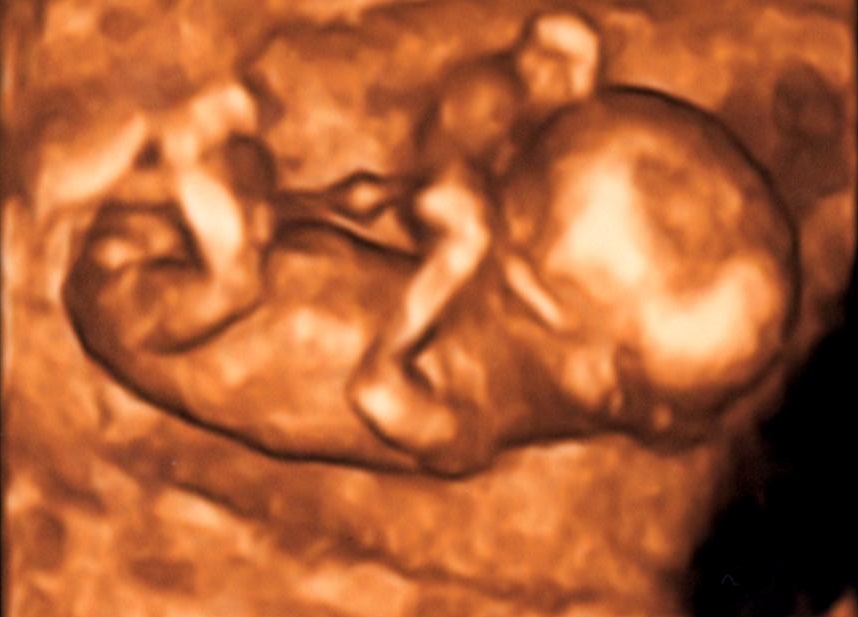

je to holka nebo kluk?

Holky, co myslíte? Holka nebo kluk :-)?